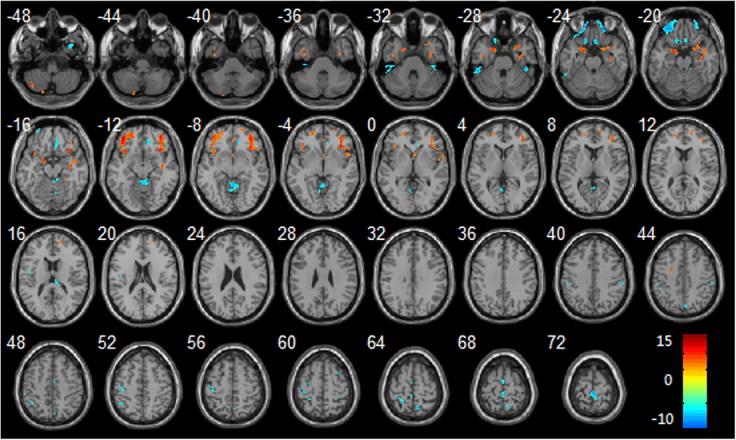

On a larger scale, a different study examined the effects of microgravity on overall brain structure and volume. Since only trained astronauts can actually go to space currently, the researchers in this study had to simulate microgravity in their volunteers (who were not astronauts) by keeping them on bedrest with their head tilted -6 degrees downwards for 30 days3. This downward tilt is currently the most accurate way to recreate many of the effects the body experiences in true microgravity4. By comparing MRI images taken before and after the 30 days of “microgravity”, they found significant losses of gray matter (or cell body) volume in the hippocampus, frontal lobes, insula, and parahippocampal gyrus. A separate group of researchers who had volunteers complete 70 days of the same head-down bedrest also found the same results5. Interestingly, when they imaged the volunteers 12 days after bed rest had ended, the decreases in gray matter were still present. What is even more concerning is that these areas are involved in memory, judgement, awareness, and decision-making — all things that are critical to maintain on space missions. Additionally, the first group found abnormalities within white matter tracts of the brain (which consist of axons, allowing different areas of the brain to communicate with each other) that mirror the abnormalities seen at early stages of Alzheimer’s disease and mild cognitive impairment.

Figure 1: Image from Li et al. Effect of simulated microgravity on human brain gray matter and white matter — evidence from MRI (2015) PLoS One 10(8):e0135835. (CC BY 4.0)